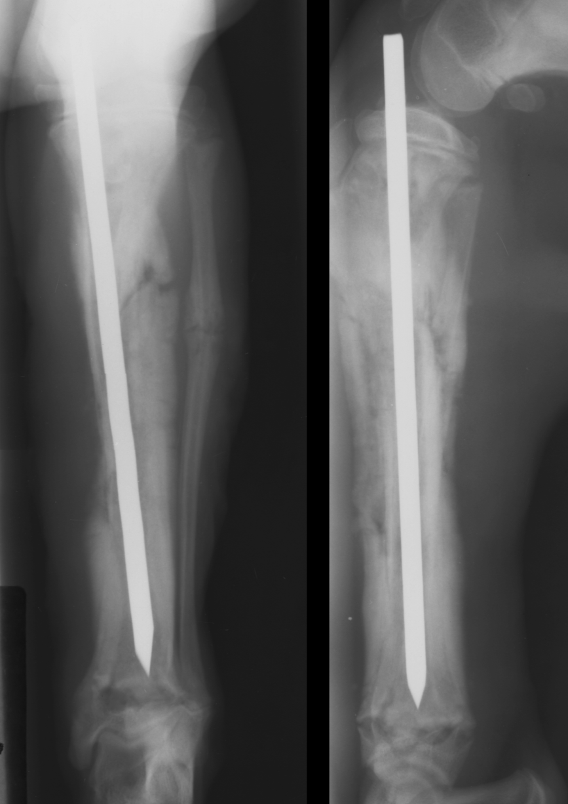

primary bone tumor signalment

large/giant dogs

bimodal age distribution

males

lung mets

monostotic - no cross joint

OSA - away from elbow, towards knee, distal tibia

AGG lesion

primary bone tumor